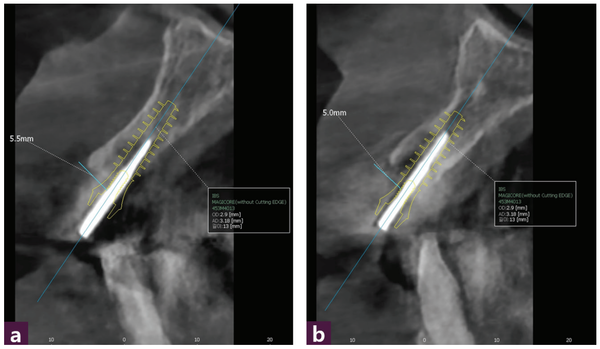

12, 22번 발치 후 GPS Drill을 이용해 구개측에 Magic Guide Pin을 삽입하고 [그림 4] CBCT 촬영 후 진단한 결과 12번은 순측의 gingiva에서 5.5mm, 22번은 순측의 gingiva에서 5 mm의 공간을 확보할 수 있었다.

Magic Guide Pin의 위치가 만족스러워 이를 바탕으로 임플란트 식립을 시뮬레이션 했고 식립 가능한 MagiCore는 직경 4.0, 길이 13mm, Magic Cuff 4로 예측됐다 [그림 5a, b].